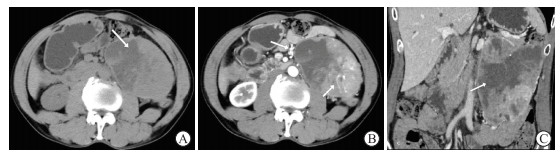

图  3   1例27岁腹部单中心型Castleman病患者的影像学表现(体检发现腹膜后占位)

A:CT平扫示腹主动脉左侧见椭圆形肿块,内可见囊变坏死,边界清楚,内部见粗大分支状钙化(箭头所示);B:CT增强动脉期示肿块实性部分明显强化,CT值达140 HU,肿块周围脂肪间隙模糊(箭头所示);C:冠状面CT增强静脉期示肿块下缘见多发肿大淋巴结环绕(箭头所示),邻近系膜增厚. CT:计算机断层扫描.